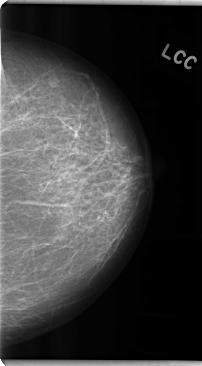

C_0285_1.LEFT_MLO

C_0285_1.LEFT_CC

LEFT_CC LINES 4752 PIXELS_PER_LINE 2624 BITS_PER_PIXEL 12 RESOLUTION 50 NON_OVERLAY

LEFT_MLO LINES 4760 PIXELS_PER_LINE 2640 BITS_PER_PIXEL 12 RESOLUTION 50 NON_OVERLAY